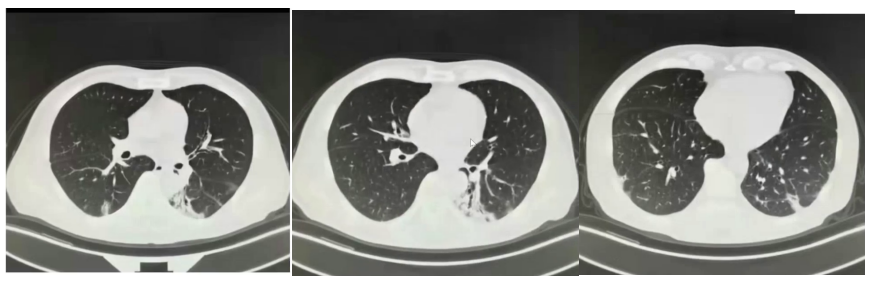

治疗一个月后病灶稳定,近期复查肺部病灶已明显完全吸收。

2021年10月起出现干咳伴发热(体温37.9℃),起初未重视,后咳嗽加剧伴咳白黏痰。11月15日于当地医院就诊,考虑肺炎,予青霉素联合阿奇霉素治疗一周,症状无改善。11月27日行胸部CT检查,提示左下肺斑片实变影,考虑继发性肺炎可能,给予泼尼松15mg BID一周、10mg BID一周治疗。治疗两周症状未缓解,且出现心悸气促,复查胸部CT病灶无吸收,遂自行停药,改服复方甘草合剂。两周后症状依旧,至第二家医院就诊,胸部CT显示肺部病灶增多变实,仍考虑继发性肺炎,予泼尼松30mg qd口服半月,气促稍有好转后又自行停药,期间辅以莫西沙星抗感染、乙酰半胱氨酸抗氧化治疗,复查胸部CT病灶仍无吸收,遂至我院。

胸部CTA:双侧胸廓对称,未见明显异常。双肺多发条索斑片影,左肺下叶为主。双侧肺门、纵隔、纵隔大血管和心脏影未见异常。纵隔内各组淋巴结未见异常肿大。双侧肋膈角和心膈角锐利。